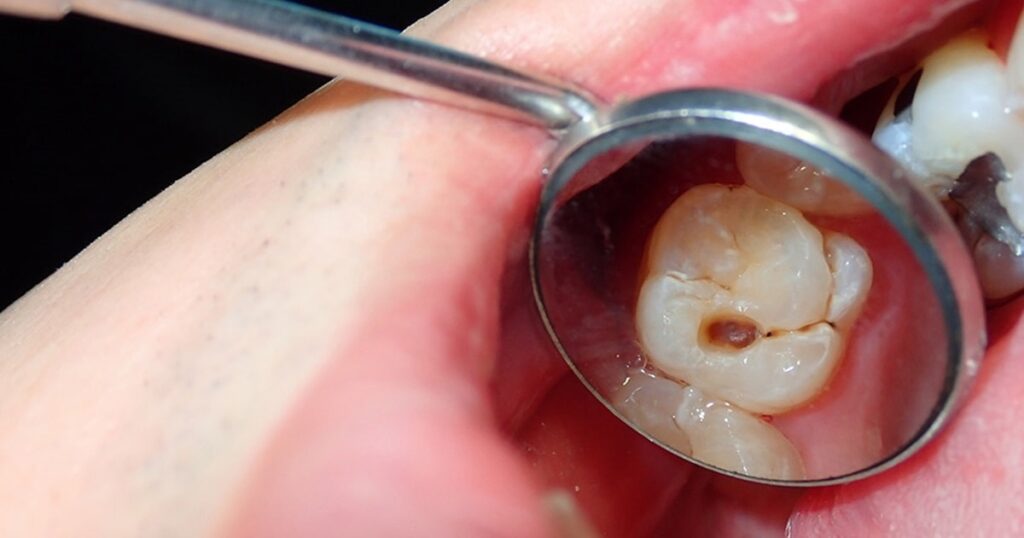

When a dentist tells you that you have a cavity, it simply means that decay has damaged the natural structure of your tooth. In such a situation, a dental filling restores the tooth’s shape and function and protects it from bacteria. It’s important to choose the right material because it affects how long the filling lasts and how much money you spend. Let’s explore different types of cavity fillings and their costs.

Amalgam is the oldest material used for dental fillings, and it’s usually the cheapest choice they have. Amalgam is famous for being incredibly durable and strong. Because it can withstand high chewing pressure, it is the standard choice for back teeth, or molars. Amalgam fillings can easily last for 10 to 15 years, and often much longer.

Composite fillings are often the most popular choice for patients today because they can blend in naturally with the color of your tooth. A significant advantage of composite material is that it bonds directly to the tooth structure. This can sometimes mean that the dentist does not need to remove a lot of the healthy tooth structure.